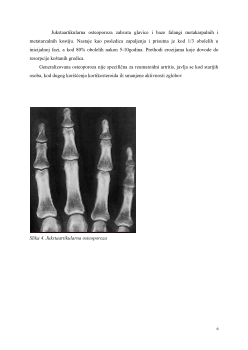

2.2. Osteoporoza